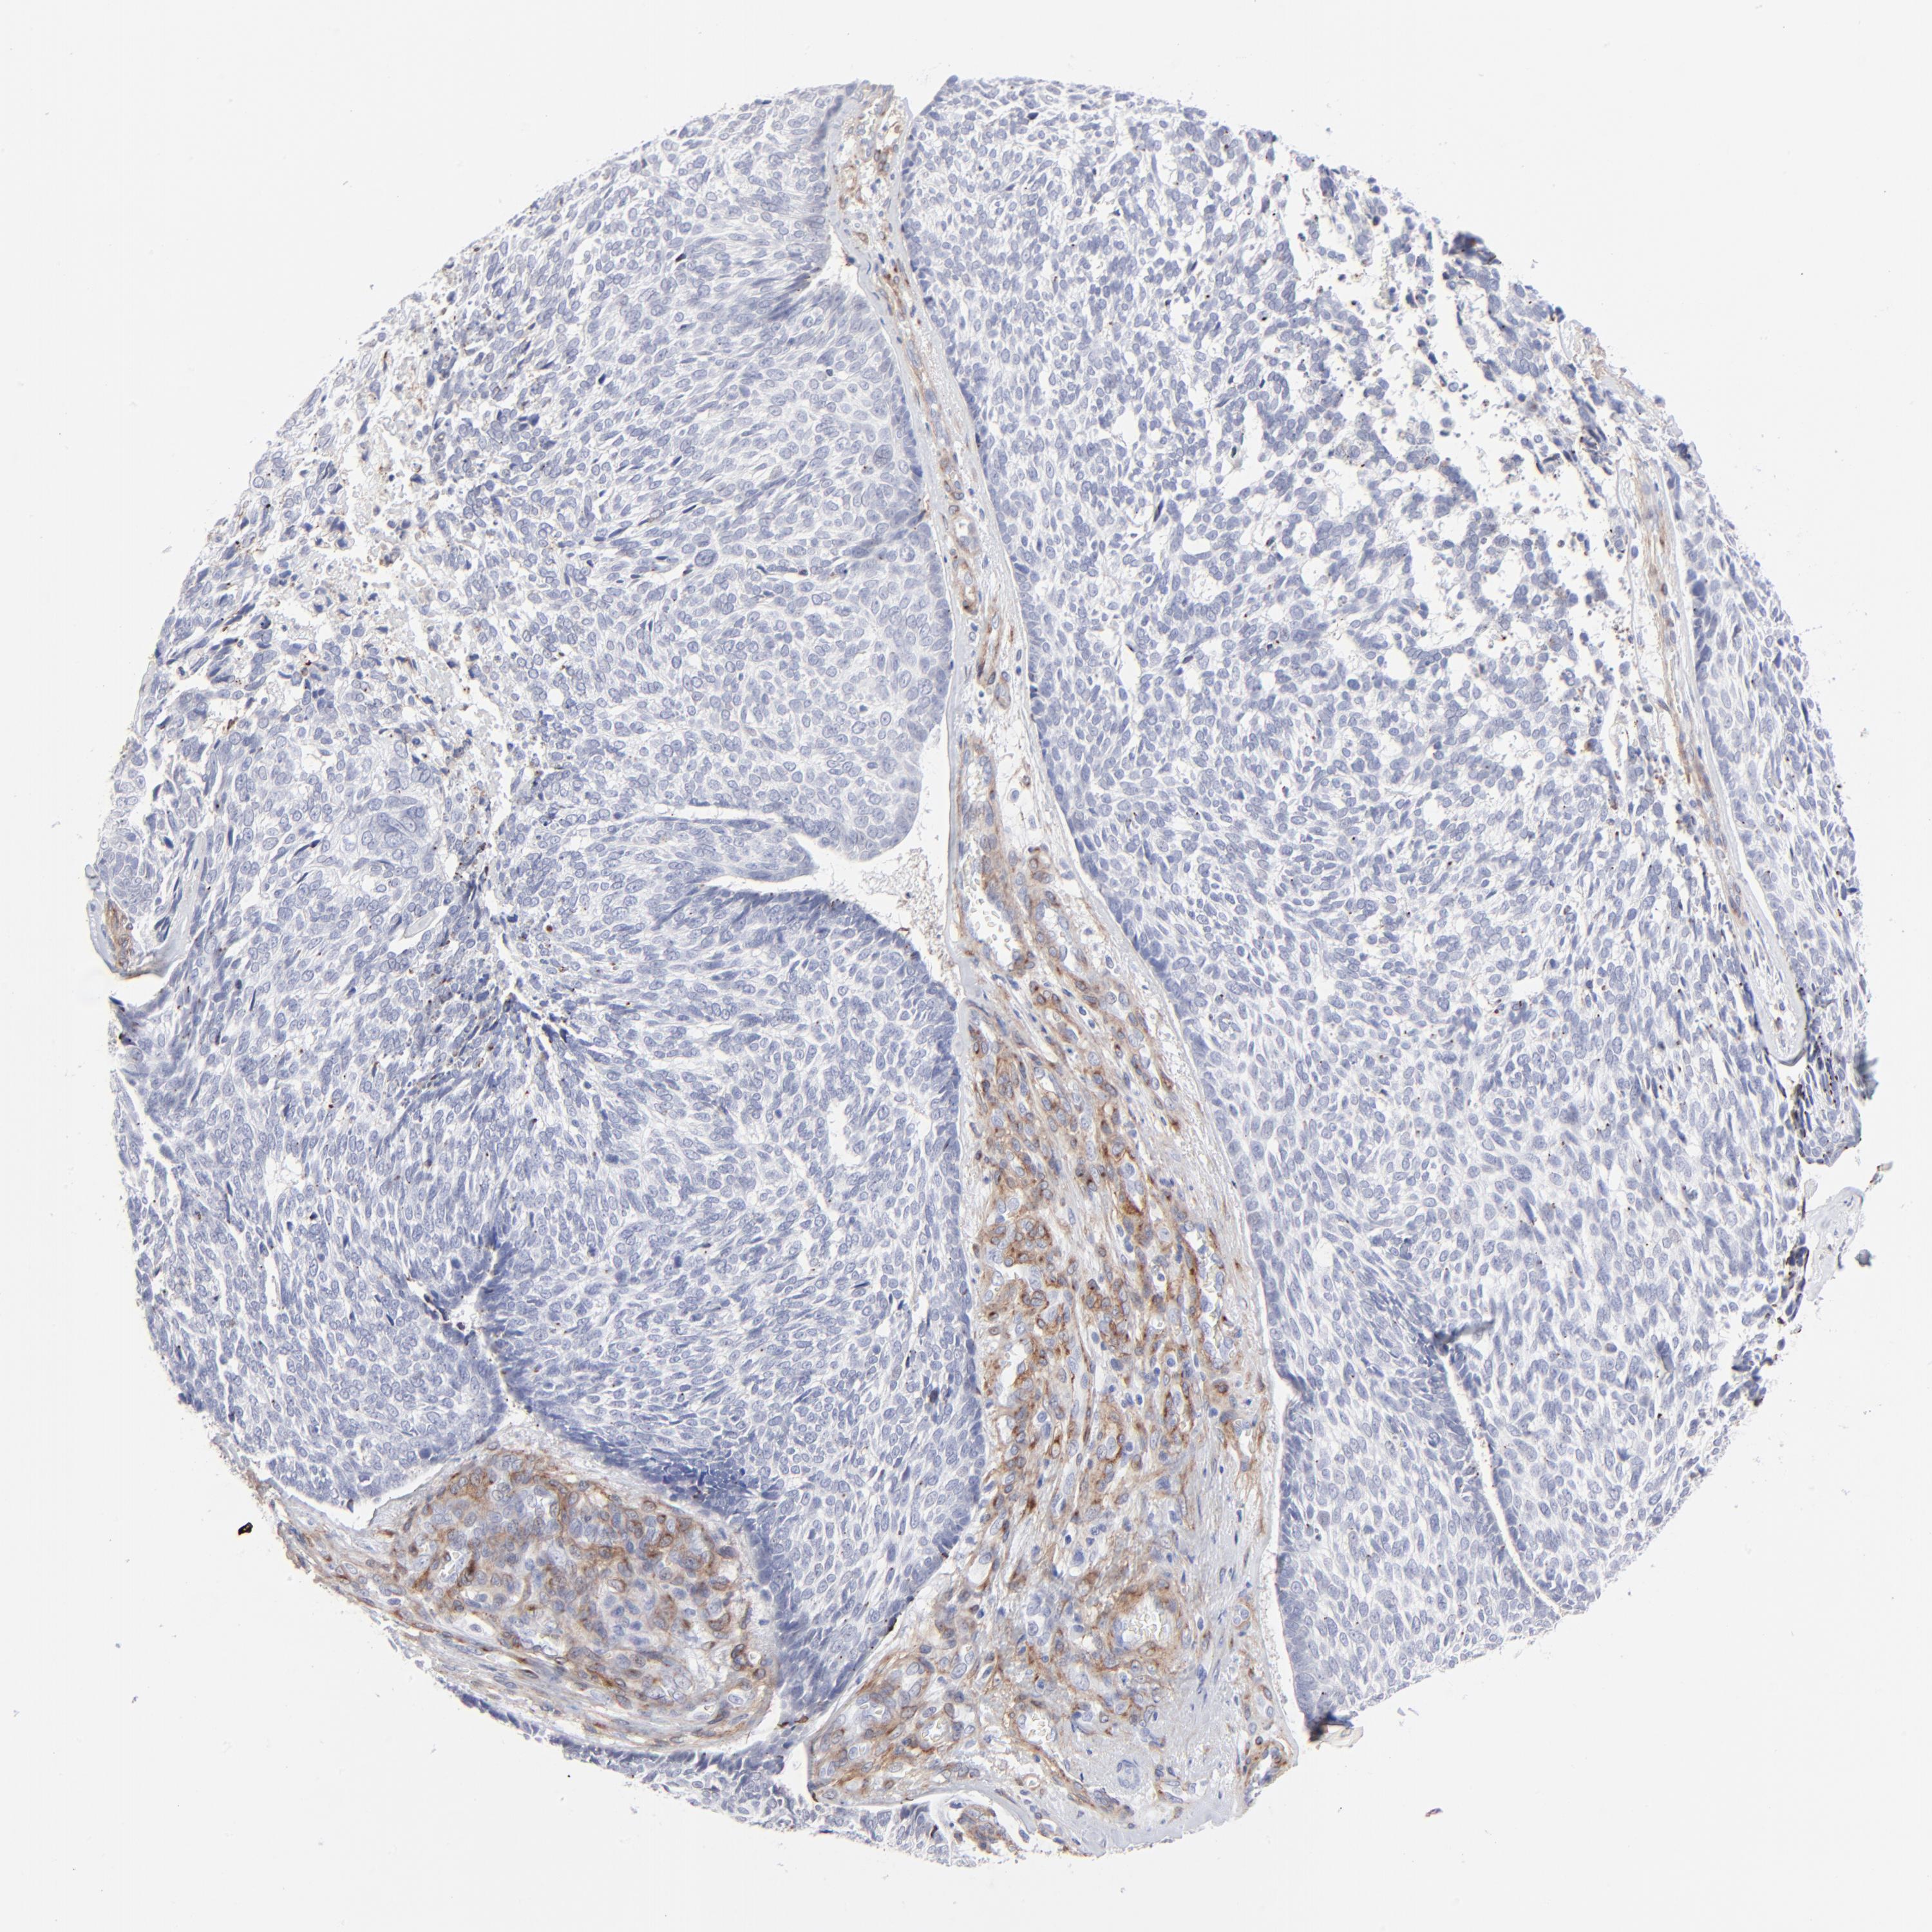

SKIN CANCER - Protein expressioni

A mouse-over function shows sample information and annotation data. Click on an image to view it in a full screen mode. Samples can be filtered based on level of antibody staining by selecting one or several of the following categories: high, medium, low and not detected. The assay and annotation is described here.

Antibody stainingi

Antibody staining in the annotated cell types in the current human tissue is reported as not detected, low, medium, or high, based on conventional immunohistochemistry profiling in selected tissues. This score is based on the combination of the staining intensity and fraction of stained cells.

Each image is clickable and will lead to virtual microscopy that enables deeper exploration of all samples and also displays staining intensity scores, fraction scores and subcellular localization as well as patient and tissue information for each sample.

Antibody CAB003842

Antibody CAB018144

Squamous cell carcinoma, NOS

Basal cell carcinoma

Squamous cell carcinoma in situ, NOS

Squamous cell carcinoma, metastatic, NOS